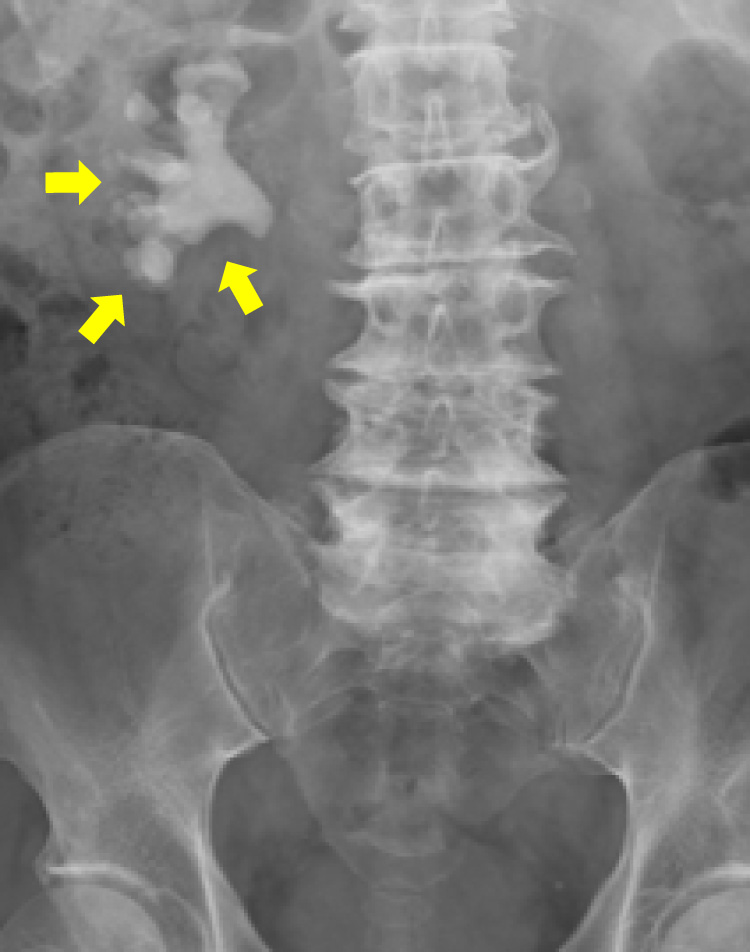

ECIRS

右完全サンゴ状結石

ECIRS後